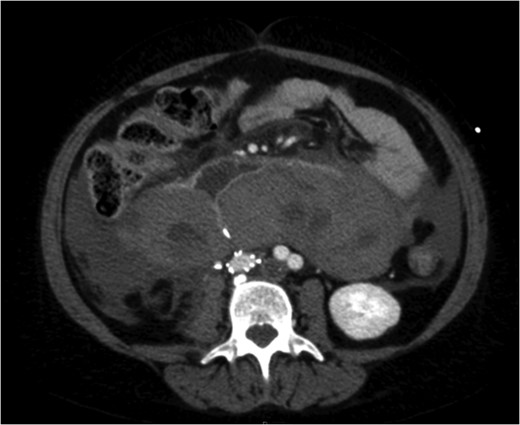

A venous phase abdominal CT demonstrating the end of the IVC filter strut penetrating the wall of the third part of the duodenum.

She had suffered an episode of septic pulmonary emboli with methicillin-sensitive staphylococcus aureus septicaemia. At the time of this event tomography and a gallium white cell scan revealed tilting of the IVC filter with strut perforation through the IVC and into the third part of the duodenum but no evidence of filter or bypass graft infection.